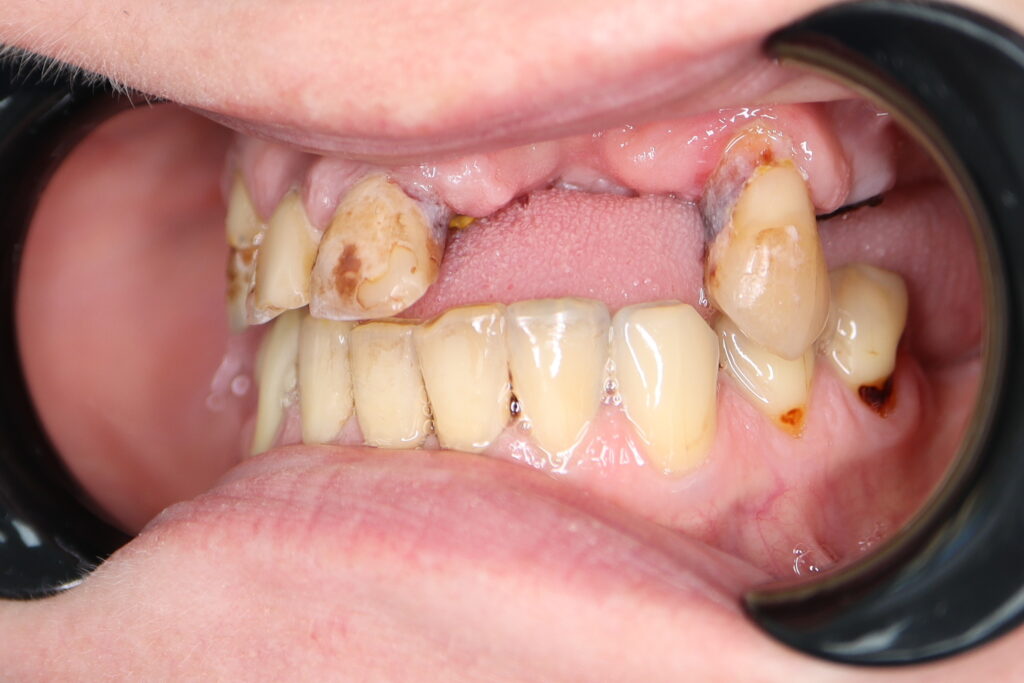

Ситуация до лечения

Жалобы: Пациент обратился с целью тотальной имплантации верхней челюсти.

Диагноз: Частичная вторичная адентия верхней челюсти.

пациент до тотальной имплантации